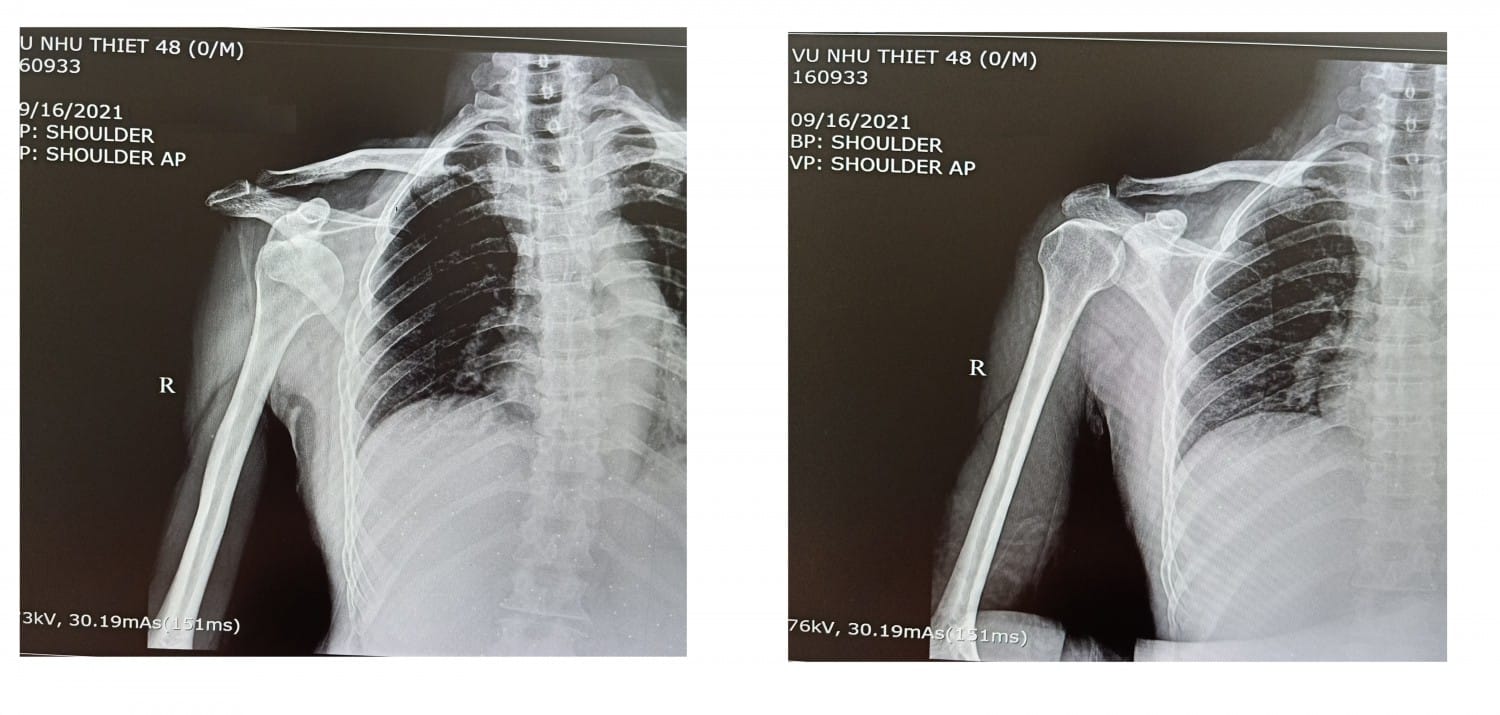

Khớp vai là một trong những khớp linh hoạt nhất trong cơ thể, cho phép cánh tay chuyển động đa hướng. Tuy nhiên, chính vì tính linh hoạt cao mà cấu trúc khớp vai lại dễ bị mất ổn định. Trật khớp vai xảy ra khi đầu xương cánh tay (chỏm xương cánh tay) bị đẩy lệch ra khỏi ổ chảo của xương bả vai, khiến hai bề mặt khớp không còn tiếp xúc đúng vị trí.

Tình trạng này có thể là trật khớp hoàn toàn (xương trật hoàn toàn khỏi khớp) hoặc trật khớp không hoàn toàn (bán trật). Ngoài ra, nếu trật khớp xảy ra nhiều lần, người bệnh có thể mắc hội chứng vai lỏng lẻo mãn tính, dễ dẫn đến biến chứng nghiêm trọng nếu không điều trị kịp thời.